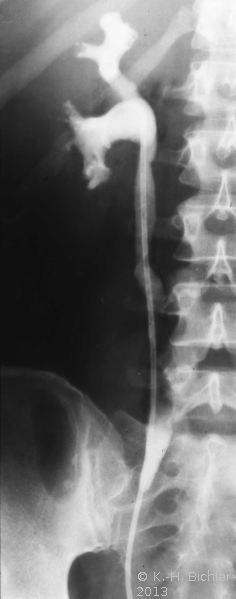

Akute nekrotisierende E. coli-Infektion. Dabei kommt es durch die Glukose spaltenden Bakterien zur Gasentwicklung im Nierenparenchym. Bei den Patienten liegt häufig ein Diabetes vor

Literatur:Schainuck, L. I. et al: "Emphysematous Pyelonephritis", Amer J Urol, 44, 134-139, 1968. Diese Form der Pyelonephritis kommt auch im Kindes- und Jugendalter vor. Das Krankheitsbild ist gekennzeichnet von Bauchschmerzen und Fieber. Die Erkrankung tritt akut mit Zeichen der Allgemeininfektion auf. Im Ausscheidungsurogramm findet sich eine Gasfüllung der ableitenden Harnwege (Abbildung 14).

Die Infektion verläuft destruktiv und prognostisch ungünstig. Bei Nichtansprechen der Therapie ist die Nephrektomie unverzichtbar.